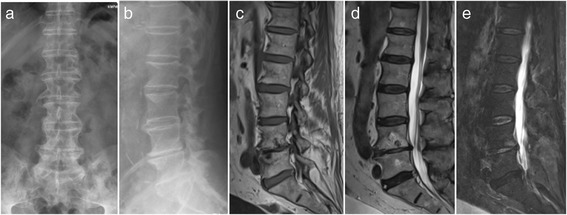

Examplary case of an 81 year old male patient presenting with immobilizing low back pain (VAS 8/10), fever and an elevated CRP serum level of 52 mg/l after 6 weeks of appropriate conservative therapy. Conventional X-ray images upon admission in an upright standing position a.p. (a) and lateral (b) Pre-operative sagittal MR T1-weighted (c) T2-weighted (d) and STIR (e) images demonstrating the bony endplate lesions at the L4/5 level

Fig. 2.

Sagittal (left) and axial (right) fat-suppressed T1-weighted MR images after IV infusion of 0.1 mmol/kg of gadoteric acid demonstrating an intramuscular abscess in the right psoas muscle at the L4/5 level (white arrow)